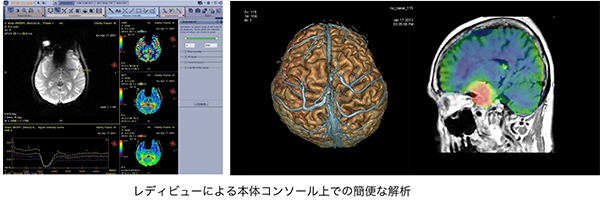

画像再構成処理・解析を効率化

・「高速リコンストラクションエンジン(63,796枚/秒)」により瞬時に画像再構成を完了。

・今まで検査後にワークステーションで行っていた画像解析処理を,本体コンソール上の「レディビュー」で実施可能に。

スキャン中の待ち時間を有効活用し,検査後の処理作業を削減します。